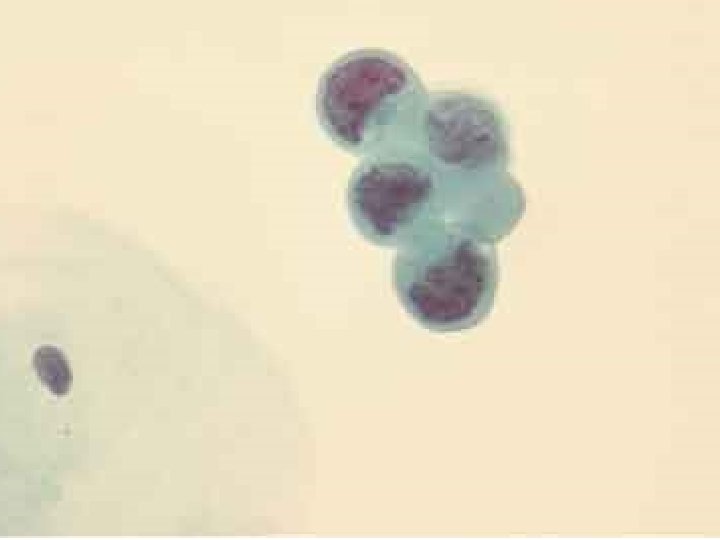

Плоскоклеточные поражения выявлены • при традиционном исследовании у 35 (19, 3%) пациенток • При жидкостной цитологии – у 76 (41, 5%) • При прицельной биопсии у 101 (55, 1%)